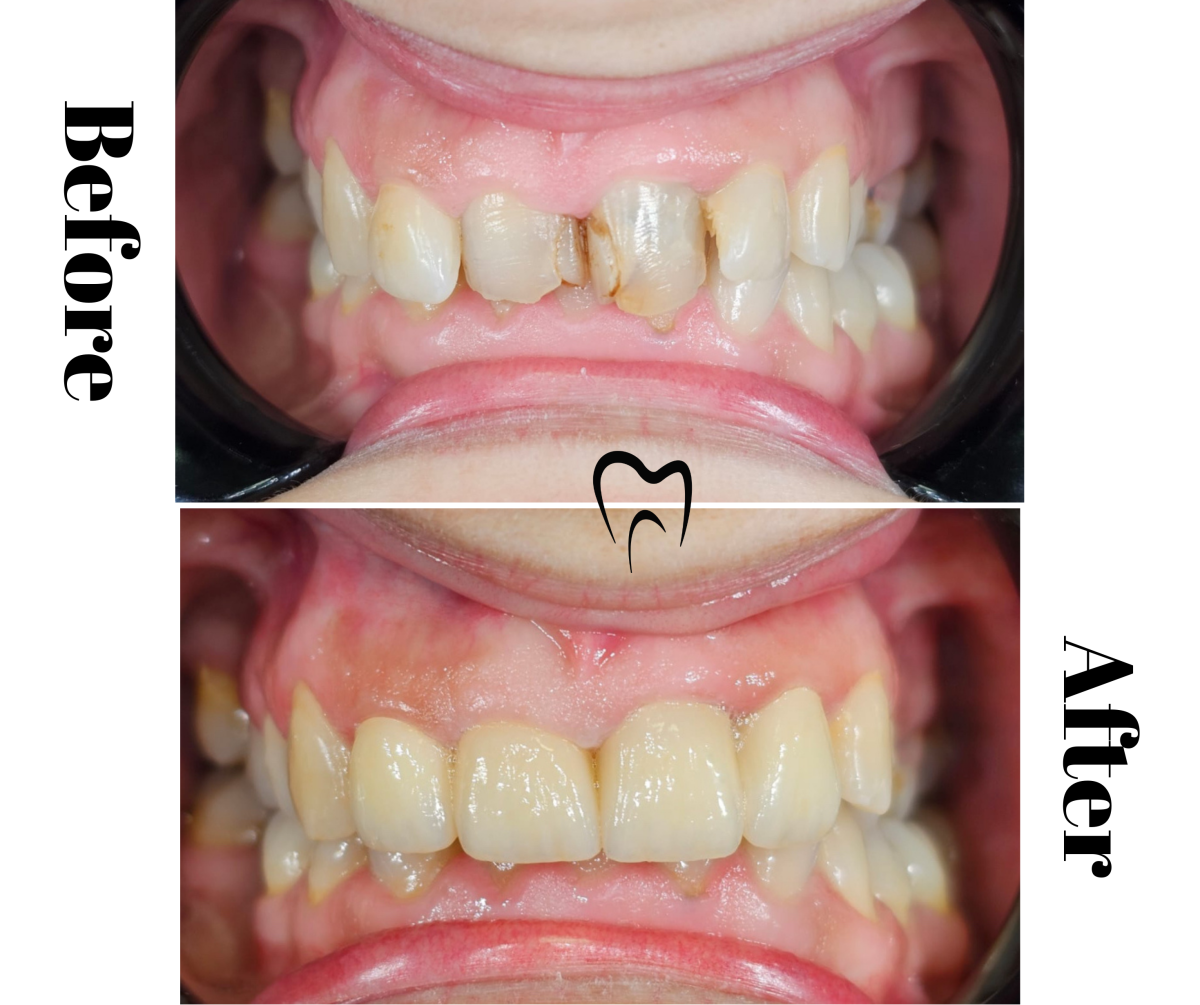

Restaurare frontală cu coronițe de zirconiu

Coroana ceramică pe suport de zirconiu